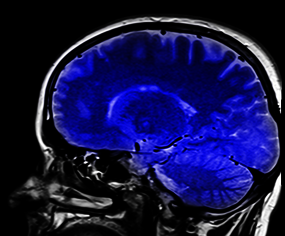

Le projet MEMORIES (ANR-21-CE36-0003) étudie les liens entre la santé mentale et la santé physique et vise à guider la recherche, la prévention et les politiques de santé publique.